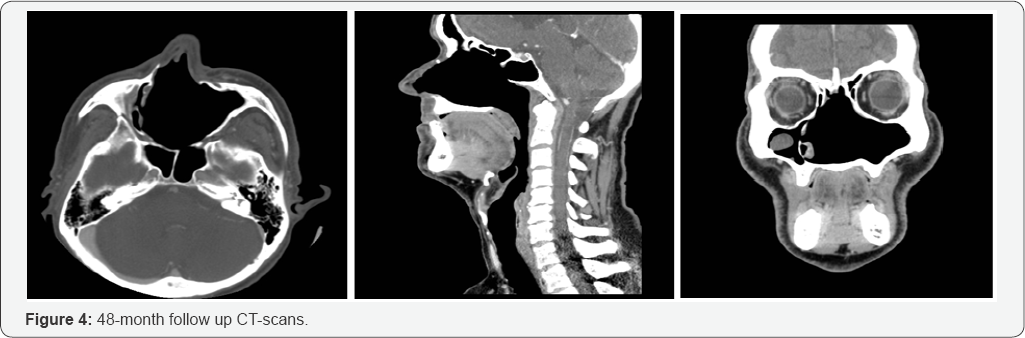

Results: Post-operative histopatological and immunoistochemical examinations confirmed a sinonasal HPC. Endoscopic and radiological 2-year follow-up did not show any tumor recurrence.

SNTHPCs can be successfully managed endoscopically [18-20]. A pre-operative embolization with superselective arterial catheterization should be done. Direct intralesional injection of acrylic glue is a feasible, safe, and effective technique for achieving presurgical devascularization, especially in case of extensive lesions with a complex vascularization. Intra-operative bleeding control can be successfully increased with local use of Floseal® Hemostatic Matrix. Since SNTHPCs should be evaluated as a tumor with a malignant potential, intraoperative frozen sections study of surgical margins followed by the histological and immunohistochemical examination should guide complete tumor resection and the subsequent follow-up.